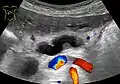

Ultrasonography of a dilated pancreatic duct (in this case 9mm) due to pancreatic cancer. -